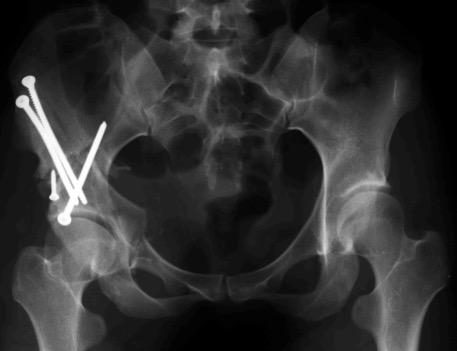

A dx risultato dopo trenta anni. La paziente lamenta dolore. Si noti l’insufficiente copertura della testa femorale

Nonostante la non perfetta sfericità della testa femorale, si esegue osteotomia periacetabolare onde migliorare la copertura della testa femorale.

Il caso fu trattato 20 anni fa.